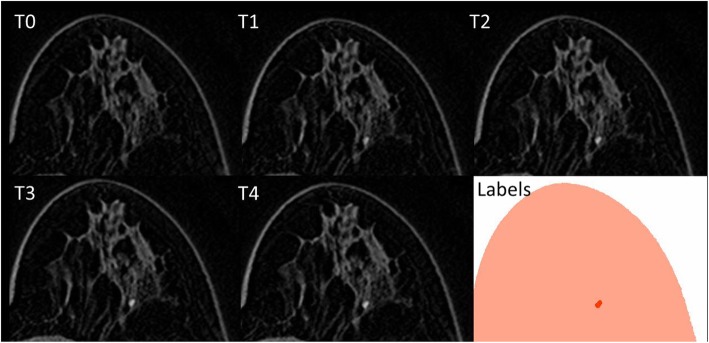

Manual lesion segmentation was carried out by one expert radiologist with more than 10 years of experience in breast MRI on the co-registered images using ImageJ [19]. Due to the spatial coherence of the unenhanced and enhanced images after co-registration, only one lesion mask was defined for each contrast-enhanced series. Images defining segmented lesion areas for each slice were defined as label images. Label and contrast-enhanced images were cropped to the bounding box containing lesions to avoid the analysis of unnecessary parts of the image. In Fig. 1, an example of a focus on unenhanced (T0) and contrast-enhanced (T1–T4) images, with its segmentation, is shown.

Fig. 1.

Breast magnetic resonance imaging showing in T0 the first (unenhanced) image and from T1 to T4 the contrast-enhanced images, where the wash-in and wash-out phenomena give information about the malignant or benign nature of the lesion. In the last image (“labels”), the segmented focus is coloured in red while normal breast tissues are coloured in pink